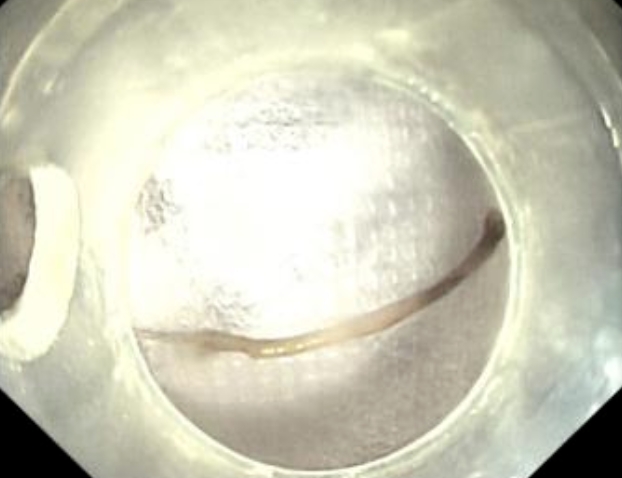

胃鏡檢查的結(jié)果令人揪心:胃底有黑色血跡附著,后壁存在直徑約2.5cm的潰瘍?cè)?,而十二指腸球部竟有一長(zhǎng)約2.5cm的棒狀異物刺入球腔,刺入處有血腫且少許滲血。消化內(nèi)科梁小波主任意識(shí)到問(wèn)題的嚴(yán)重性,立刻組織普外科、影像科、麻醉科進(jìn)行院內(nèi)會(huì)診。

影像科通過(guò)腹部CT提示十二指腸球區(qū)異物存留,但未見(jiàn)明顯穿孔。普外科鄭樂(lè)副主任結(jié)合CT結(jié)果及患者臨床表現(xiàn),精準(zhǔn)判斷為十二指腸球部異物損傷伴出血,且未導(dǎo)致穿孔,建議優(yōu)先嘗試內(nèi)鏡下取出異物及止血,必要時(shí)再行外科手術(shù)。麻醉科李秀蒲主任則根據(jù)患者復(fù)雜病史,制定了安全的麻醉方案:充分液體復(fù)蘇、備血后可行靜脈全麻,必要時(shí)轉(zhuǎn)為氣管插管全麻,為手術(shù)安全提供了有力保障。

△CT結(jié)果提示